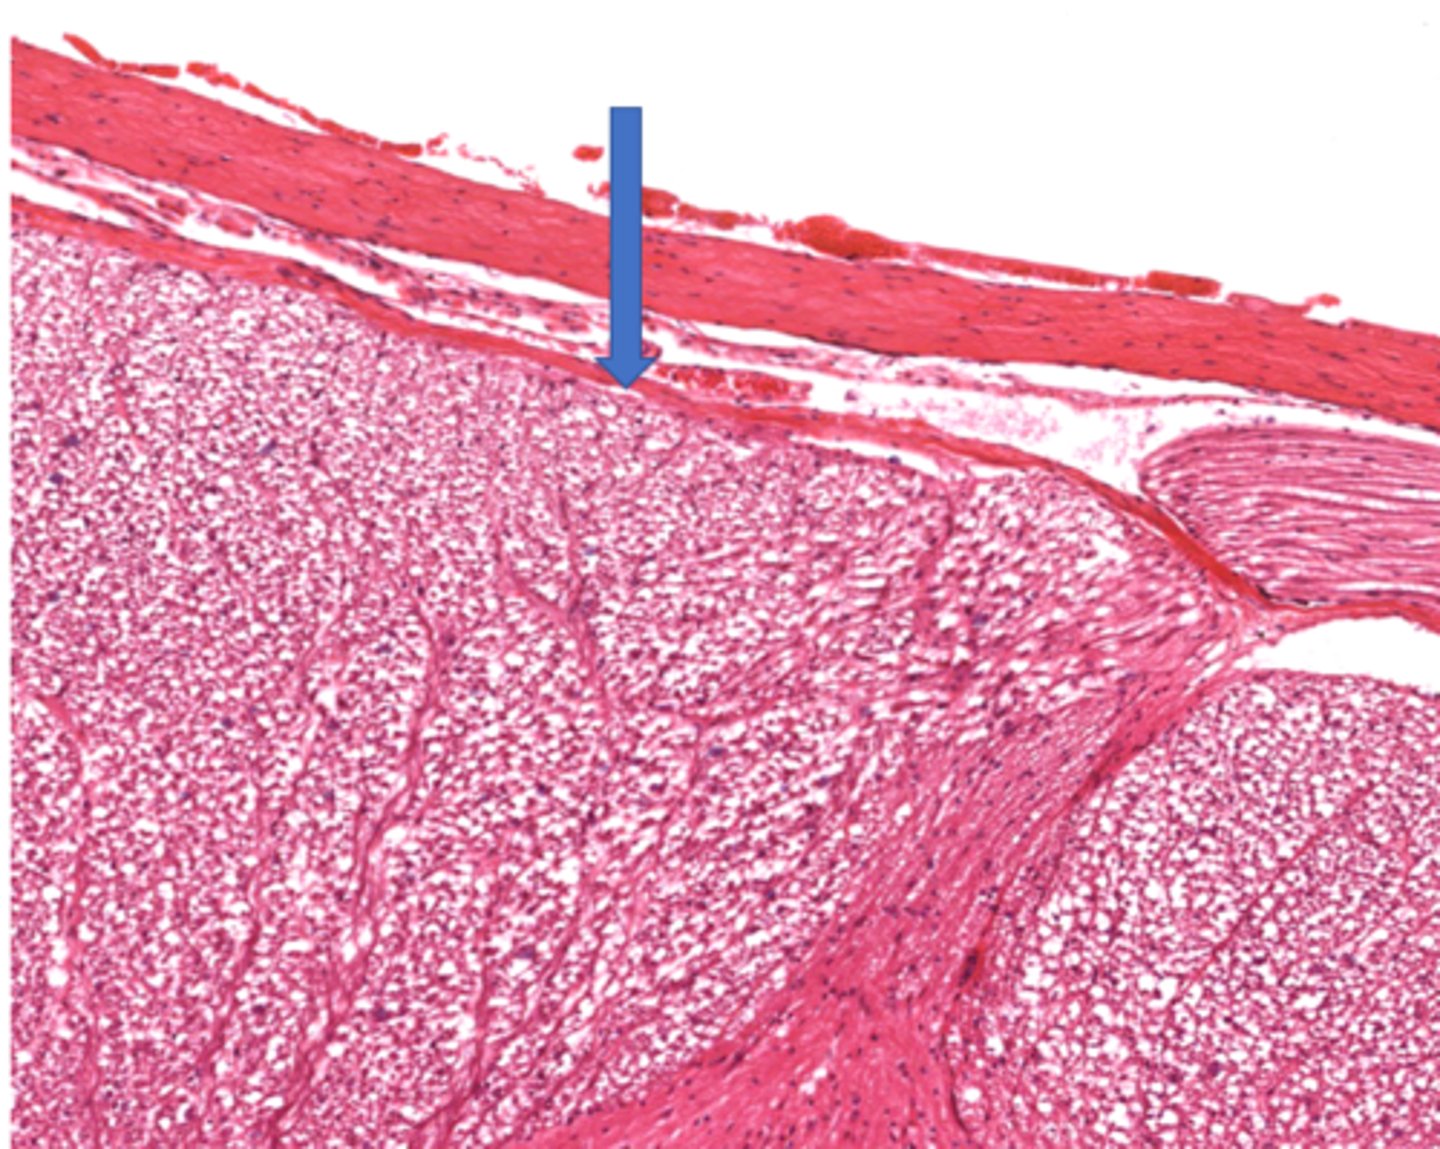

Identify the part of the meninges

pia mater

arachnoid

dura mater